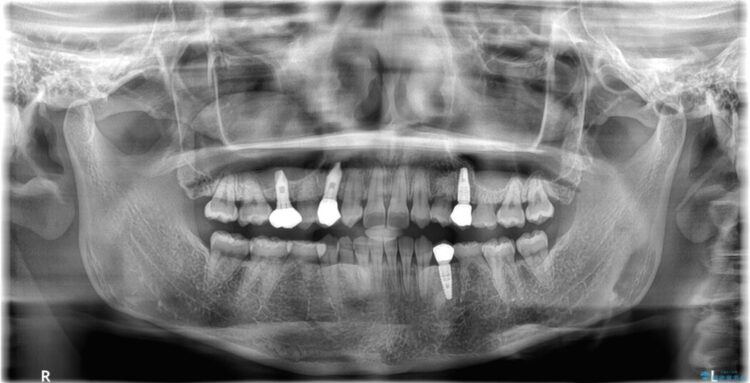

【総合歯科治療】後続永久歯の欠損

- 患者様:30代女性

永久歯が中途半端に生えかけているとの主訴で来院されました。

まずインビザラインで歯並びを改善し、その後インプラントにて咬合回復を行うこととしました。

捻転が強い部分のみワイヤーの部分矯正での治療をしています。